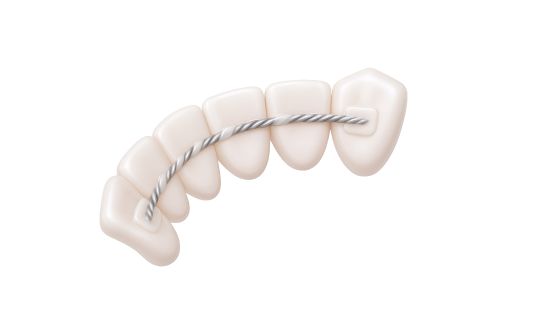

Закрытие рецессии десны. Чтобы восстановить ткани десны и защитить корень зуба, врач использует методику трансплантации мягких тканей. Лечение периимплантита. Чтобы устранить воспаление вокруг имплантата, врач тщательно очищает мягкие ткани от бактериального налета и инфицированных участков. Иногда назначается медикаментозная терапия. В случае необходимости хирург выполняет коррекцию тканей, чтобы стабилизировать имплантат и предотвратить его потерю. Пластика уздечки и слизистых тяжей. Если уздечка языка или губ укорочена, проводится коррекция. Процедура проходит под местной анестезией и длится всего несколько минут. Она позволяет устранить дискомфорт, улучшить функциональность и предотвратить развитие патологий зубного ряда и дефектов речи.